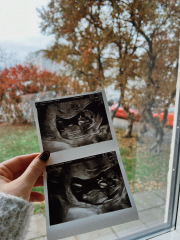

Newtothis5 · 10/02/2017 20:27

Hey all! So when my friends and relatives have been expecting I've loved using 'theories' to guess the gender and quite a lot of the time I have been right. Based on skull and nub theory. We had our scan today and baby is measuring 12 week 5 days. I really wish I had asked for a nub picture as I can't see it on this pic. I think I am swaying more team blue. What do you all think? :)